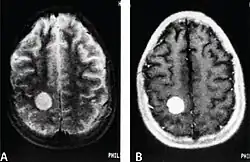

Brain MRI of a patient diagnosed with primary cardiac angiosarcoma that metastasised to the brain.

MRI scans use strong magnetic fields and radio waves to create an image, while CT scans use X-rays. MRI scans produce more detailed images of bodily structures, particularly soft tissues including the brain,[13] and are better at detecting CNS metastases than CT scans. However, CT scans are sometimes used for the initial imaging modality due to their lower cost and efficiency in screening for multiple conditions.[14]